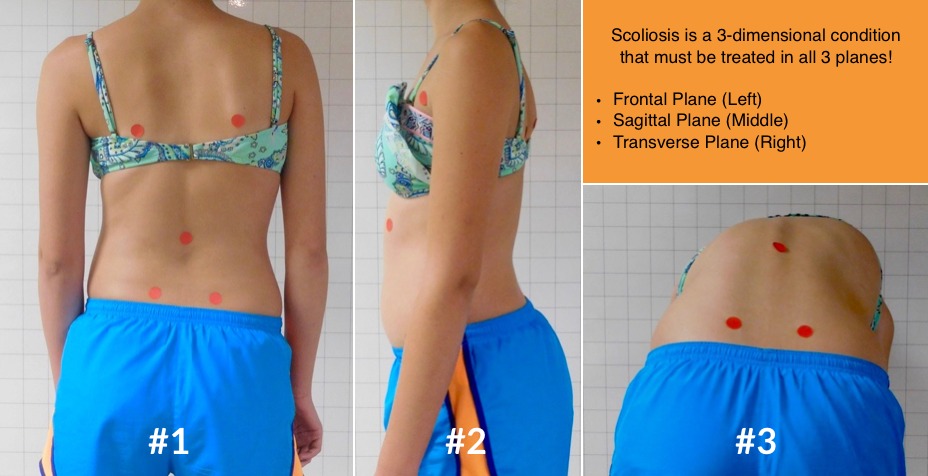

ولكن في الواقع، الجنف ليس انحناءً جانبيًا فقط، بل هو تشوه ثلاثي الأبعاد يشمل:

الانحناء الجانبي (المستوى الأمامي)

الدوران الفقري (المستوى المحوري)

التغيرات في تقوس الظهر الطبيعي (المستوى السهمي)

لذلك، أصبح من الضروري دراسة العمود الفقري والقفص الصدري في الثلاثة مستويات معًا لفهم مدى استجابة الطفل للحزام.

5. شكل القفص الصدري

وقد صنفت الدراسات القفص الصدري إلى نوعين رئيسيين:

قفص صدري أفقي

قفص صدري مائل أو متدلٍ

النتائج أظهرت أن الأطفال ذوي القفص الصدري الأفقي يستجيبون بشكل أفضل للحزام، خاصة إذا كان الدوران الفقري أقل.